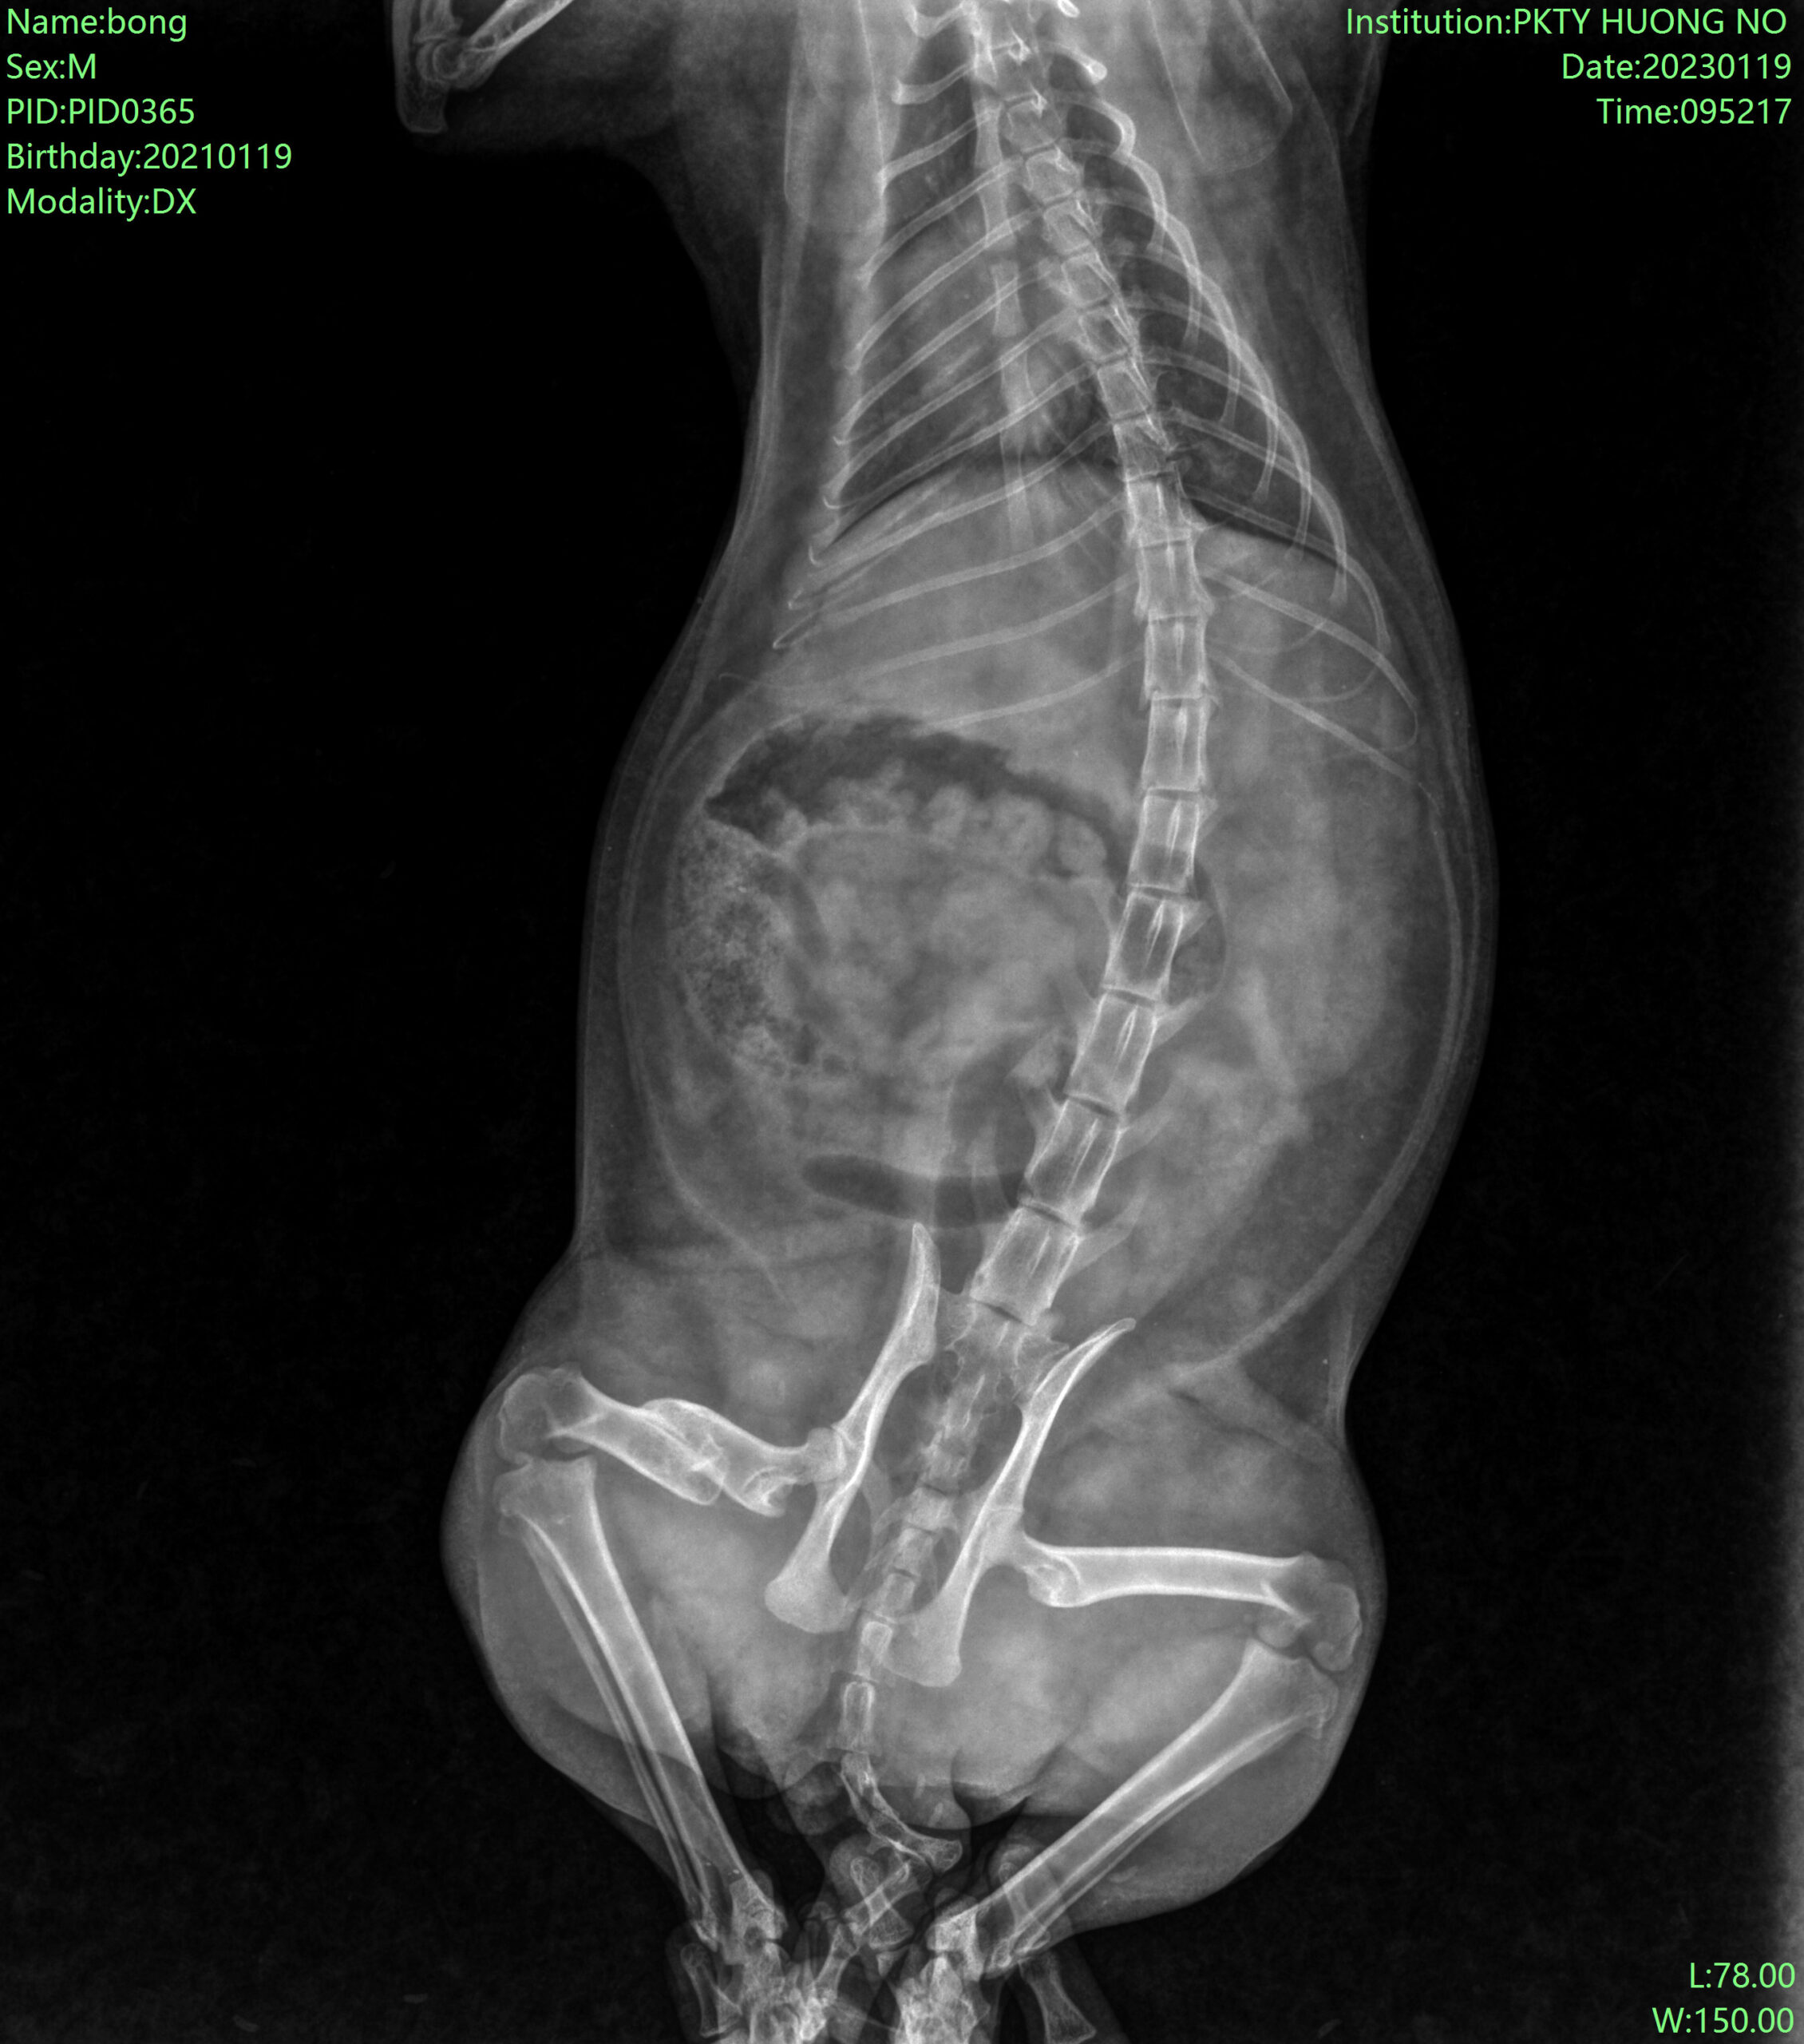

1. Ca phẫu thuật xương đùi bé cún bị tai nạn:

Trước phẫu thuật: